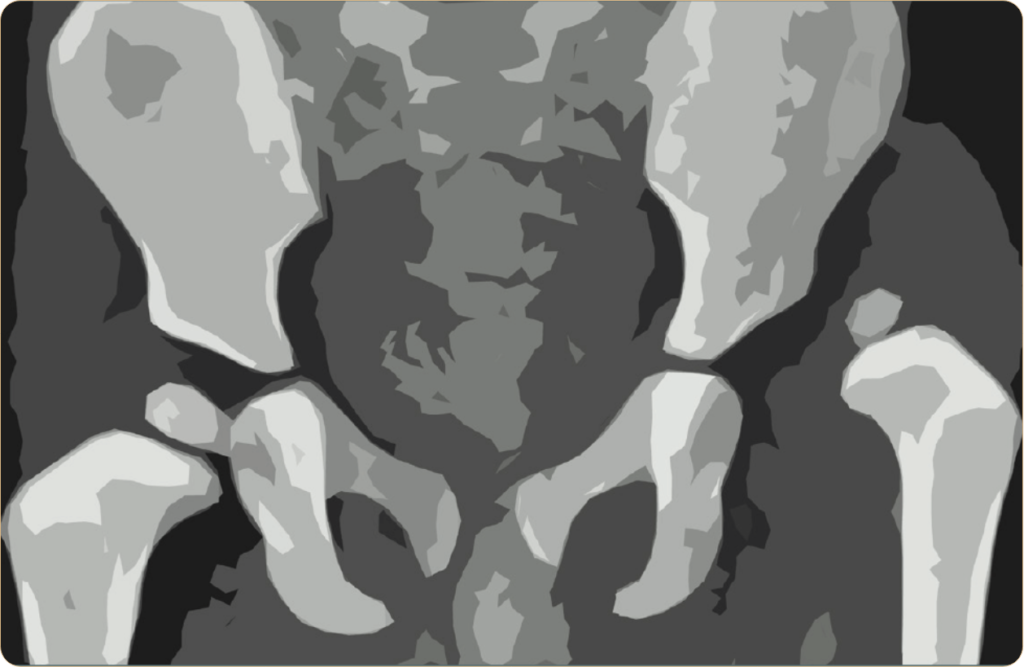

Seu bebê recebeu diagnóstico ou suspeita de displasia do quadril

O pediatra solicitou ultrassom ou raio-X e você está insegura sobre o resultado

Existe histórico familiar de displasia